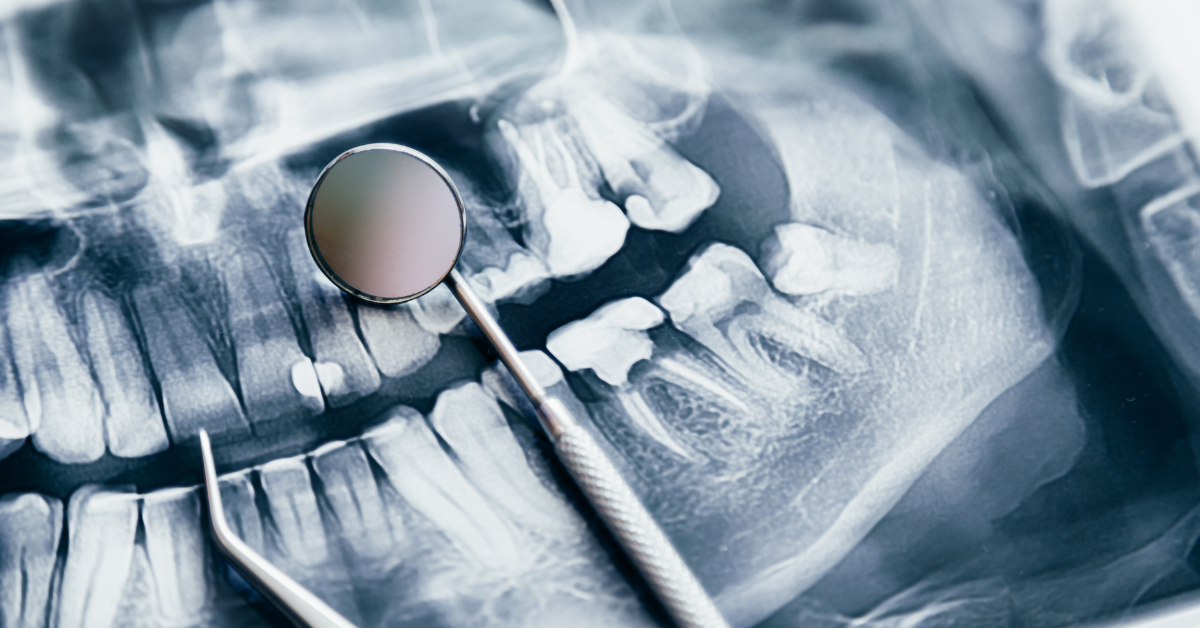

Çene Kırıkları ve Travmatik Yaralanmaların Tedavisi

Çene kırıkları (mandibula ve maksilla), trafik kazaları, düşmeler, spor yaralanmaları veya darbe sonucu oluşabilir. Tedavi, fonksiyonel ve estetik bütünlüğü sağlamak amacıyla yapılır.

- Alveolar Kırıklar:Dişlerin bulunduğu kemik bölgesinde meydana gelir.